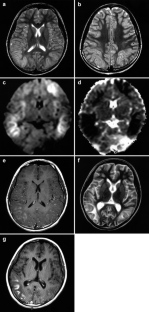

We document the MRI features in six patients aged 5–14 years with acute encephalitis following measles. The diagnosis was made on a characteristic morbiliform rash and detection of specific IgM and IgG antibodies. The symptoms of encephalitis occurred 1–11 days after the appearance of the rash. All patients underwent MRI within 1–4 days of the onset of neurological symptoms. Diffusion weighted images (DWI) were obtained in three patients. In all patients, T2-weighted images showed widely distributed, multifocal high signal in both cerebral hemispheres with swelling of the cortex, with bilateral, symmetrical involvement of the putamen and caudate nucleus. The lesions had showed low apparent diffusion coefficients. Three patients showed subacute gyriform haemorrhage, and asymmetrical gyriform contrast enhancement on follow-up MRI.

Fig. 2a-g.